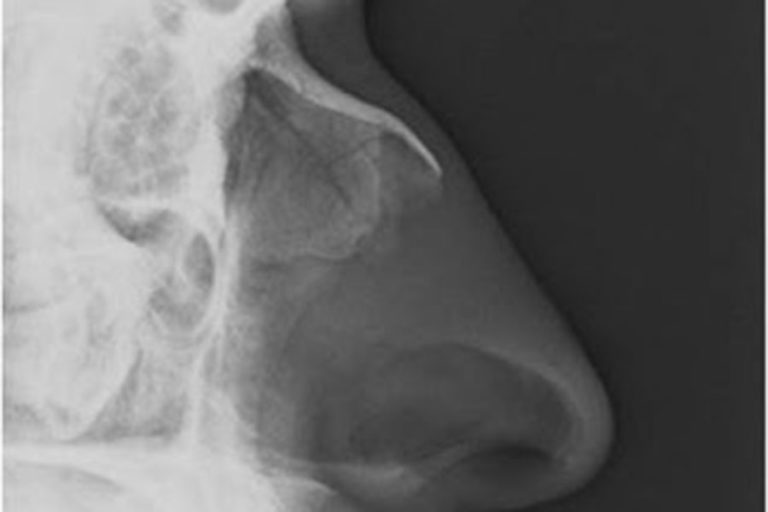

Does the patient in your case have a nasal fracture?

According to Dr. Greg Gilbert, from Stanford University Medical Center, x-rays of the nose serve no purpose in diagnosing nasal fractures: “A nasal fracture is a clinical diagnosis and not one that should be made…

What is a nasal fracture, really?

Nasal fractures are the most common facial fracture and the third most common fracture of any bone in the body. They most frequently occur as a result of assault or motor vehicle collisions. What we…